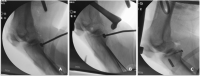

Surgical technique: We present a PCL tibial inlay reconstruction technique using a set of instruments involving three tools (a slot cut, a bone plug positioner, and an impactor).

Conclusion: This set of instruments allows a more reproducible posteromedial approach and to produce a PCL tibial slot in a posterior cruciate ligament inlay reconstruction with the patient supine in bicruciate ligament injury reconstruction.